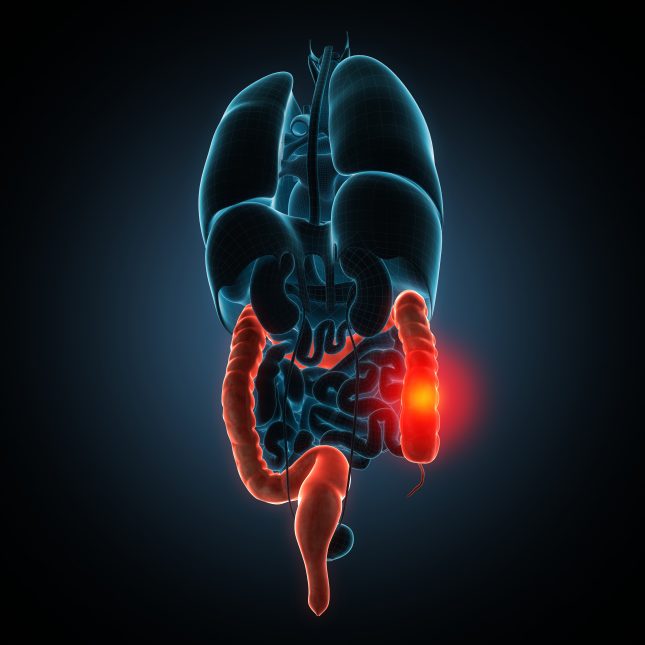

נגיף הקורונה הפך במהרה למצב חירום בריאותי עולמי ורבות דובר על קבוצות הסיכון שחשופות אל הווירוס יותר מאשר השאר האוכלוסיה. תת-קבוצה בקבוצה הסיכון היא מטופלים עם מחלות מעי דלקתיות (IBD) שנמצאים בסיכון מוגבר, במיוחד כאשר הם סובלים ממחלה פעילה ונוטלים תרופות מדכאות חיסון. המאפיינים והתוצאים של קורונה במטופלי IBD אינם ברורים.

באיטליה, אשר בה ההתמודדות עם המגיפה היתה קשה במיוחד, נערך עוקבה תצפיתי פרוספקטיבי ונכללו בו חולי מעי דלקתי עם זיהום קורונה. החוקרים אספו נתונים אישיים, נתונים הקשורים למחלה (סוג, טיפול ורמת פעילות), תחלואה נלווית (על פי Charlson Comorbidity Index או CCI), נתונים הנוגעים לסימנים ותסמינים של קורונה. כמו כן בחנו את תוצאי ההידבקות בקורונה אצל מטופלים אלה (דלקת ריאות, אשפוז, טיפולים נשימתיים ומוות).